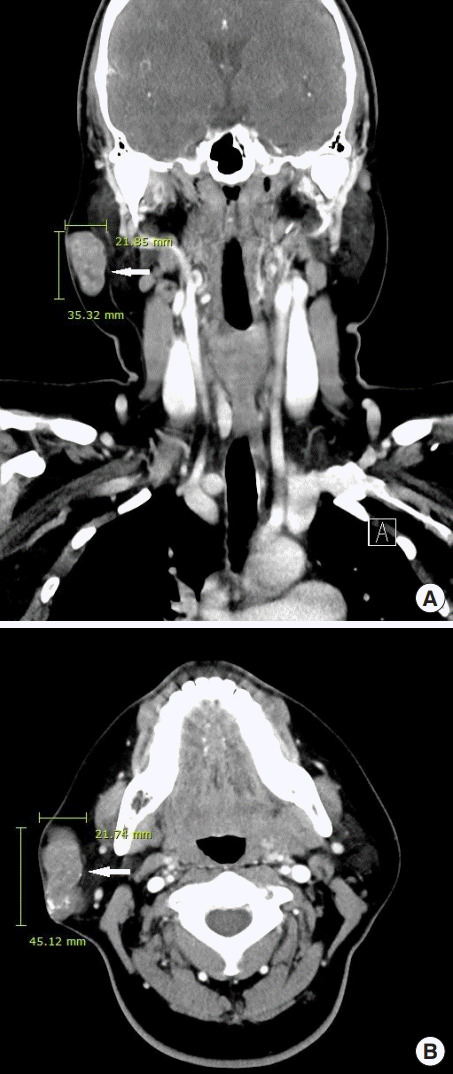

诊断时为35岁的张雨绮(女,化名)右侧腮腺区有肿块,就诊于佳学基因检测合作医院的整形外科。 肿块直径约 1 cm,张雨绮因无临床症状而拒绝手术切除。 然而,在怀孕的中晚期,肿块的大小增加到 5 厘米(图 1),并且变得疼痛。 分娩后肿块停止生长。 触诊肿块时,患者报告疼痛从腮腺区放射至耳后区。 病灶摸起来温暖、坚硬、淡蓝色和分叶状。 由于临床症状加重,患者同意接受手术切除肿块。

毛母质瘤是一种良性皮肤肿瘤,起源于分化为毛母质细胞的表皮原始基底细胞。 大多数毛母质瘤的直径约为 1 厘米,而直径为 5 厘米或以上的则被归类为巨大毛母质瘤。 头颈部毛母质瘤的鉴别诊断包括皮脂腺囊肿、骨化性血肿、鳃残余、耳前窦、淋巴结肿大、巨细胞瘤、软骨瘤、皮样囊肿、退化性纤维黄瘤、异物反应、皮肤骨瘤。 准确诊断毛母质瘤需要放射影像学和组织病理学检查。 其组织病理学特征包括外围的细胞簇(包括有核基底样细胞)和中心的无核影细胞(也称为“鬼细胞”)呈圆形排列。 巨大的毛母质瘤通常与外伤有关,并且有时会在外伤事件后观察到溃疡或坏死组织物质的局灶性经表皮消除。

在本报告中,我们描述了一名 34 岁女性在右侧腮腺区域患有巨大毛母质瘤的病例。 最初发现肿块时,直径为 1 厘米,无症状。 然而,在患者怀孕期间,肿块长至 5 厘米并出现症状。 患者称,最初检测到肿块后右侧腮腺区域未发生外伤。